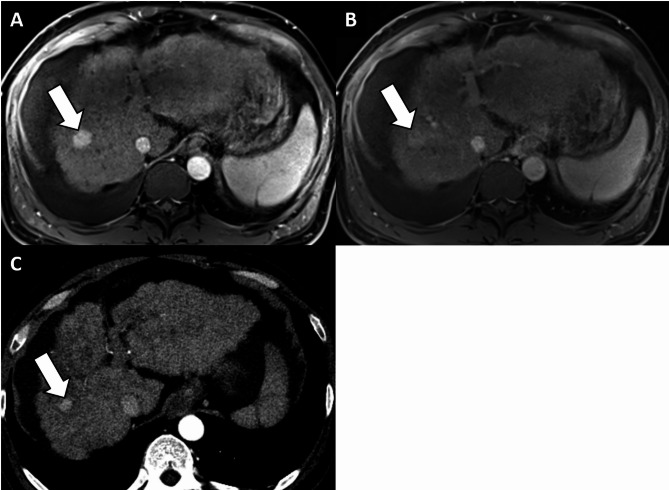

背景:阈值生长(TG)在肝细胞癌(HCC)成像中的应用在主要指南中仍然存在争议。本研究旨在探讨TG在肝成像报告和数据系统(LI-RADS)标准下肝癌诊断中的诊断意义。方法:在这项单中心回顾性研究中,三名放射科医生独立评估了2010年1月至2022年11月期间连续接受肝移植的患者的移植前肝胆剂增强MR图像和先前的CT/MR图像,使用LI-RADS v2018。TG定义为≥50%的尺寸增加≤6个月。肝脏作为参考标准。使用Fisher精确检验比较hcc和非hcc之间的TG频率,并使用Fleiss κ统计评估观察者间的一致性。在考虑TG为主要特征和不考虑TG为主要特征的情况下,评估LI-RADS第5类在HCC诊断中的诊断性能。麦克尼马尔试验用于比较结果。结果:纳入158例患者(平均年龄59.1±7.5岁;130例男性),280例观察(207例hcc, 5例非hcc恶性病变,68例良性病变)。有44例(15.7%)观察到TG。观察者间对TG的一致性为中等(κ = 0.280)。将TG作为主要特征可显著提高LI-RADS第5类诊断HCC的敏感性(33.8% vs. 40.6%)。结论:将TG作为LI-RADS第5类的主要标准可提高肝移植候选人HCC的诊断敏感性,对特异性影响最小。然而,TG显示了一个可变的观察者之间的协议。试验注册:不适用。

Methods: In this single-center retrospective study, three radiologists independently evaluated pre-transplantation hepatobiliary agent-enhanced MR images and prior CT/MR images using LI-RADS v2018 in consecutive patients who underwent liver transplantation between January 2010 and November 2022. TG was defined as a ≥ 50% size increase in ≤ 6 months. Explanted livers served as reference standards. Frequencies of TG between HCCs and non-HCCs were compared using Fisher's exact test, and interobserver agreement was assessed using Fleiss κ statistics. The diagnostic performance of LI-RADS category 5 in the diagnosis of HCC was assessed with and without considering TG as a major feature. McNemar tests were used to compare results.

Results: The cohort included 158 patients (mean age, 59.1 ± 7.5 years; 130 males) with 280 observations (207 HCCs, 5 non-HCC malignancies, and 68 benign lesions). TG was identified in 44 (15.7%) observations. Interobserver agreement on TG was moderate (κ = 0.280). Incorporating TG as a major feature significantly enhanced the sensitivity of LI-RADS category 5 in diagnosing HCC (33.8% vs. 40.6%, p < 0.001) without compromising specificity (100.0% vs. 94.5%, p = 0.125).